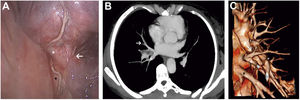

A 56-year-old woman with a history of lung adenocarcinoma in the right lower lobe stage cT3N2 treated with neoadyuvant radio and chemotherapy was referred for surgery. Due to N1 involvement, a VATS right lower bilobectomy was performed. Having sectioned inferior pulmonary vein (IPV) (Fig. 1, black asterisk), we observed the sixth segmental vein (V6) (Fig. 1, white asterisk) draining into the middle lobe vein (MLV) (Fig. 1, white arrow). Preoperative CT-scan and tridimensional reconstruction confirmed our findings (Fig. 1B, C).

Commonly, V6 is the uppermost and smaller segmental tributary of the IPV.1 Nagashima et al. reported an uncommon drainage pattern in which V6 drained into the superior pulmonary vein.2 We describe a different variation: V6 draining into the MLV. Knowing this rare anatomical variant can help thoracic surgeons prevent intraoperative injuries during bilobectomies, right lower lobectomies and S6 segmentectomies. Careful examination of the vessels at preoperative CT-scan should be mandatory before starting any procedure.